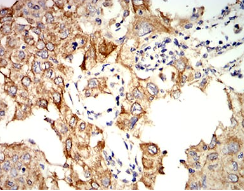

KRT10 Mouse Monoclonal antibody[1C3D9]

Species Reactivity:    Human,Monkey

IHC    1/200 - 1/1000